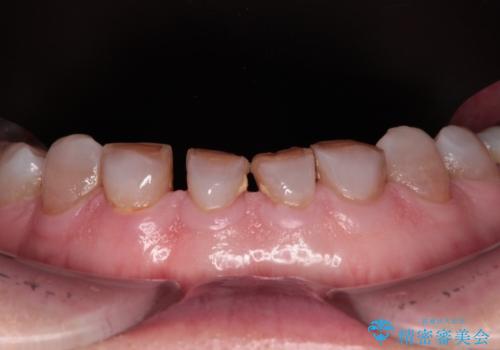

- 前歯の変色や欠損による隙間を気にして来院された患者様です。

上顎前歯は樹脂による変色を覆い隠す処置が行われていましたが、汚れが溜まりやすく厚みも増している状態でした。

上顎前歯は樹脂を外し、下顎前歯の隙間はそれぞれの歯を大きくするように補綴治療を行うことで隙間を埋めることとしました。